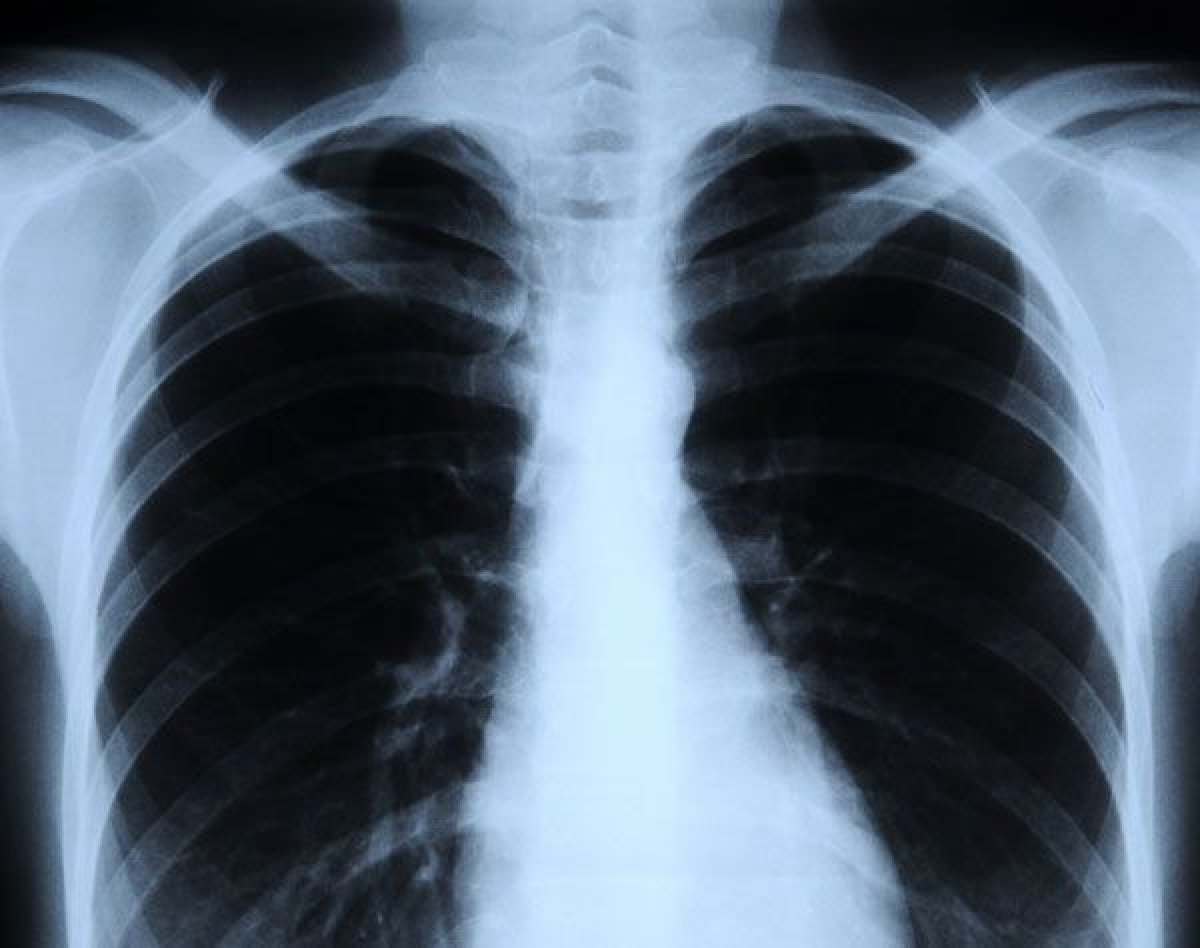

Yapay zeka röntgenden ırkları tespit ediyor

İnsanların röntgen ve tomografi görüntülerinden ırk tahmini yapan bir yapay zeka, % 100'e yakın doğru tahminde bulundu. Nasıl çalıştığı anlaşılmayan sistemin, ten rengini belirleyen melanin pigmentine bakarak tahminde bulunduğu düşünülüyor.

Tıbbi amaçlı kullanılan yapay zekanın röntgen ve tomografi görüntüleriyle insanların ırklarını tahmin edebilmesi doktorları endişelendirdi. Zira bilim insanları, bilgisayarın bunu nasıl yapabildiğini bilmiyor.

Araştırma ekibi ilk olarak yapa zeka sistemini söz konusu görüntülerle eğitti. Bunlarda hastaların ırkları da yazıyordu. Daha sonra ırkların belirtilmediği görüntü kümeleri gösterildi. Modellerin çoğunda yapay zeka sistemi, insanların ırkını yüzde 95 ila yüzde 99 arasında doğru tahmin etti.

Uzmanlar, yapay zekanın bunu nasıl yapabildiğini bilmiyor. Ten rengini belirleyen pigment olan melaninle ilgisi olduğu düşünülüyor. Araştırmacılar, sistemin daha koyu renklerin daha yüksek seviyede melanin içerdiğini tespit ettiğini ve bu bilgiyi ırk tahmin etmede kullanabileceğini söylüyor.